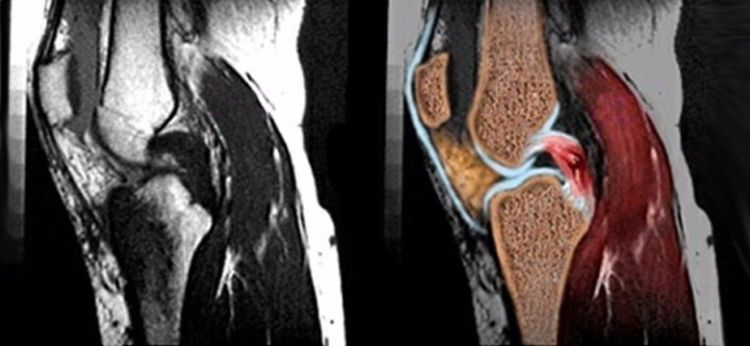

正常后交叉韧带的MRI表现:各序列均为低信号。矢状位韧带为凸面向后的弓形,边缘光滑。

矢状位上弓形的后交叉韧带形成一个135度夹角。

MRI阅片时要注意半月板-股骨韧带对后交叉韧带的影响,其在矢状位后交叉韧带弓形的上下方可见到小的、边缘清晰的低信号影。